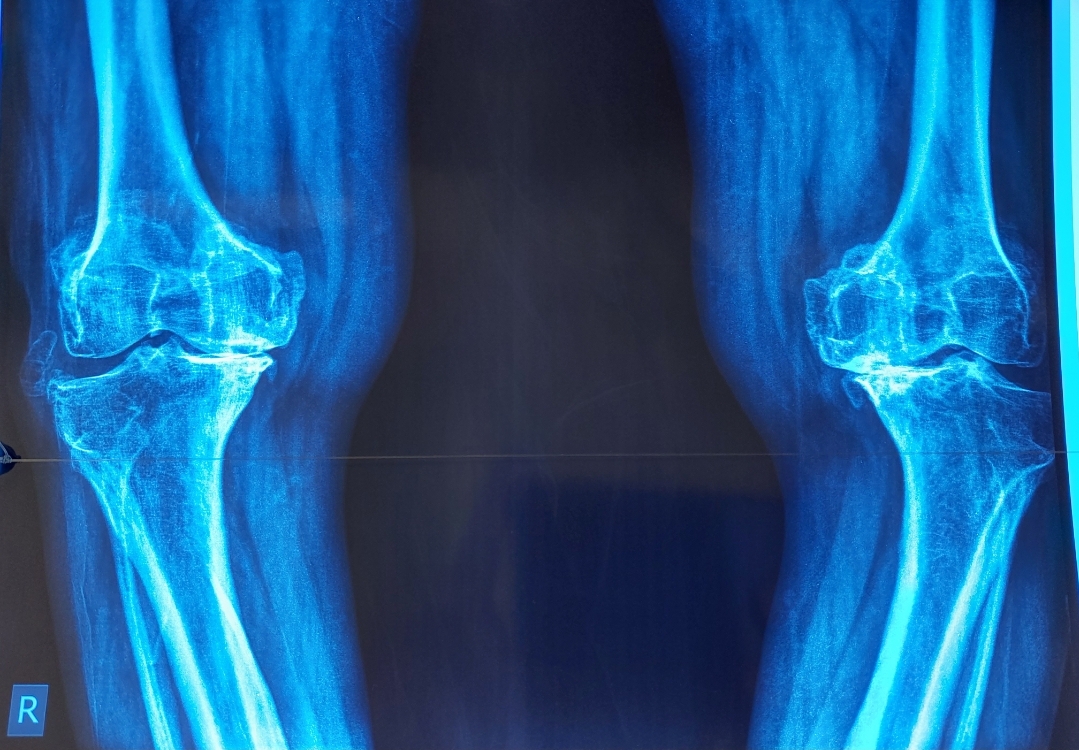

Total Knee Replacement Surgery: A Comprehensive Guide

Recovering After a Total Knee Replacement: What to Expect?

Understanding Types of Total Knee Replacement Surgery | Best Orthopedic Surgeon in Lahore